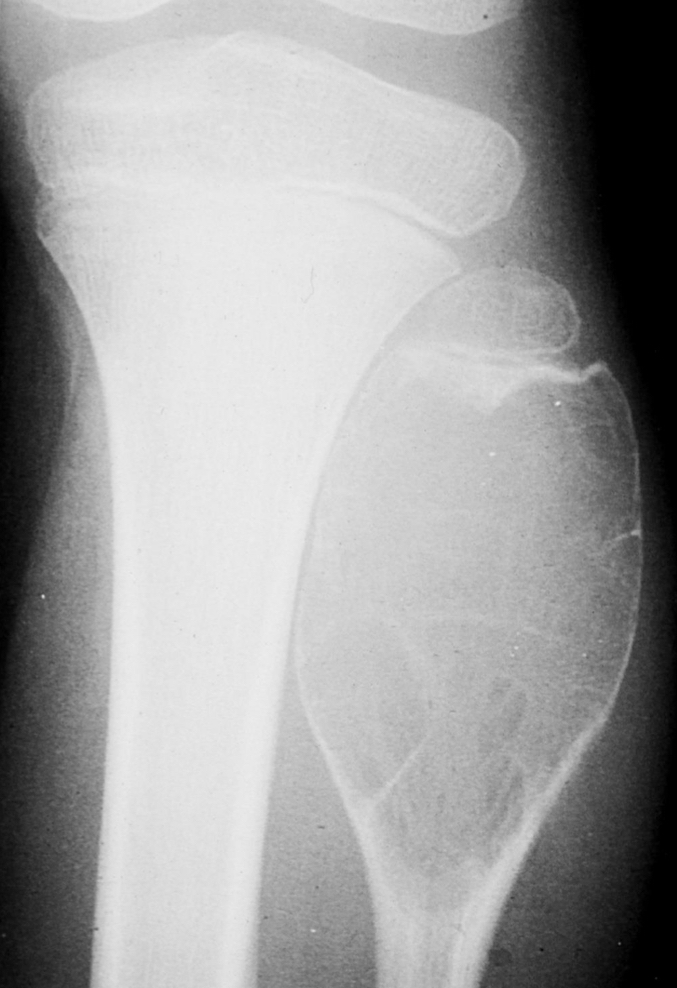

what is this?

malignant transformation rate? what does it turn into if it does transform?

ollier disease

25-50%; chondrosarcoma